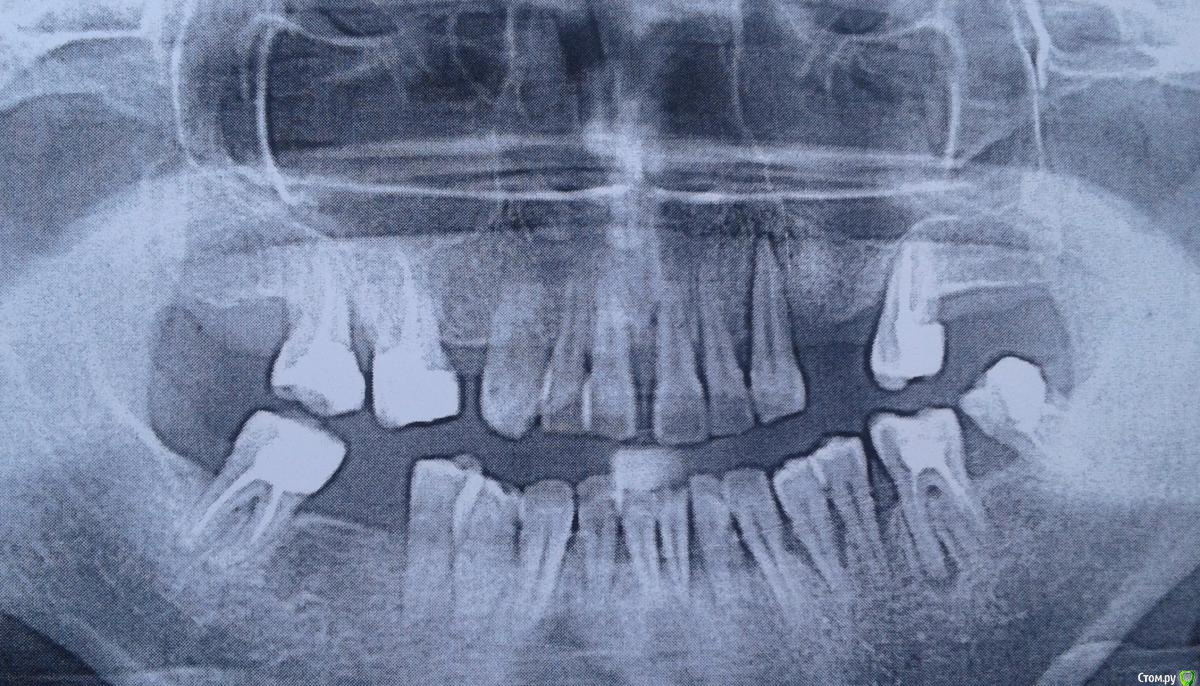

Нюра_А Опубликовано 26 октября, 2016 Автор Поделиться Опубликовано 26 октября, 2016 (изменено) Спасибо за отзыв на сообщение! Сделала на обеде снимок Изменено 26 октября, 2016 пользователем Нюра_А Ссылка на комментарий

Jurai Опубликовано 26 октября, 2016 Поделиться Опубликовано 26 октября, 2016 я бы еще на КТ посмотрела. как минимум, переделать ОПТГ. что-то меня фронтальный отдел нижней челюсти цепляет, на обоих представленных снимках. Ссылка на комментарий